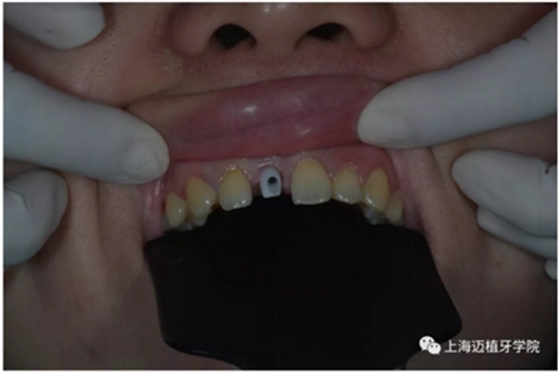

戴牙前口內(nèi)照片:

去除愈合基臺(tái):

口內(nèi)個(gè)性化基臺(tái):